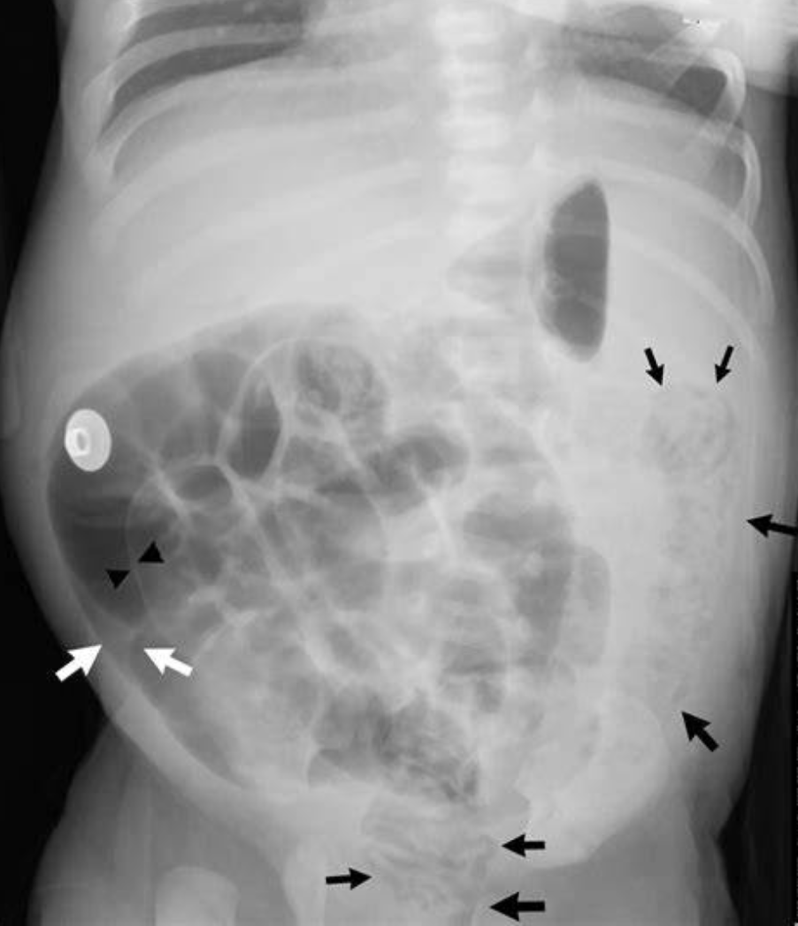

These findings on an XR make you concerned for NEC

pneumatosis

What is pneumatosis intestinalis

what does a football sign mean on XR?

Seen with massive pneumoperitoneum

In supine position air collects anterior to abdominal viscera

pneumoperitoneum